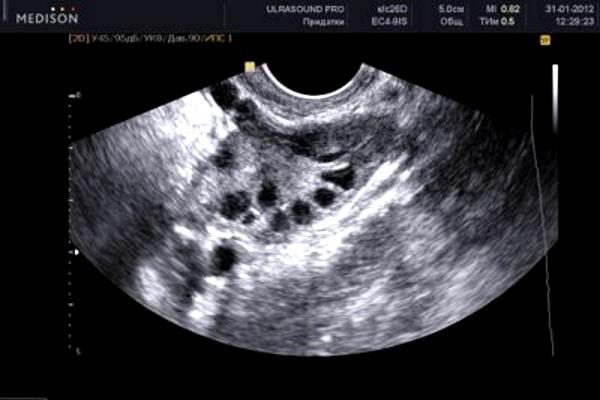

Методы ультразвуковой диагностики являются наиболее результативными и достоверными способами определения состояния маточного органа и нормы в эндометрии при климаксе.

В норме М-ЭХО матки не должно быть более 5 миллиметров. При величине данного показателя в пределах 6 мм, максимум 7 мм — становится необходимым динамичный контроль над толщиной эндометрия в менопаузе с повторными ультразвуковыми исследованиями через 3 и 6 месяцев. Хотя такие показатели еще допускаются и 7 мм – это в некоторых случаях нормальная толщина.

Если толщина эндометрия в менопаузе превышает показатель 8 мм, то это говорит о развитии патологического процесса. В данной ситуации для того, чтобы поставить точный диагноз, специалист проводит диагностическое выскабливание маточной полости.

В том случае, когда эндометрий в менопаузе, то есть непосредственно его толщина, сильно превышает показатель 12-13 мм, проводится раздельное выскабливание слизистой и отправляется на гистологическое исследование полученного биологического материала из маточной полости.

Как было выше сказано, в эндометрии есть определенная норма его толщины, превышение которой говорит о патологии. Толщина эндометрия выявляется посредство ультразвукового метода диагностики.